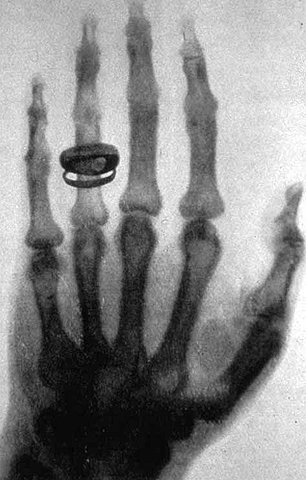

• Primera imagen

Primera imagen

Roentgen tomo su primera imagen en un brazo fracturado y se la envió a Britsish Medical para analizar su diagnóstico y lo increíble de los resultados.